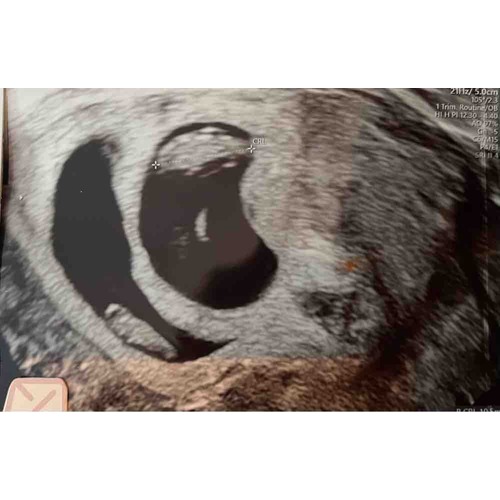

Mijn echo van afgelopen maandag bij 7+4. Helemaal onderin gelegen met het hoofdje rechts, twee ‘stompjes’ die uit moeten groeien tot armpjes. Daarboven het vruchtzakje. Zo bijzonder hoe ze dat allemaal al kunnen zien! Ik ben benieuwd naar de volgende echo.